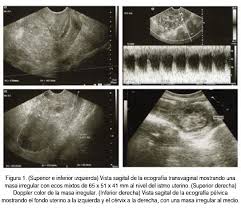

Aborto Diferido Como Origen De Una Enfermedad Trofoblastica Persistente Progresos De Obstetricia Y Ginecologia